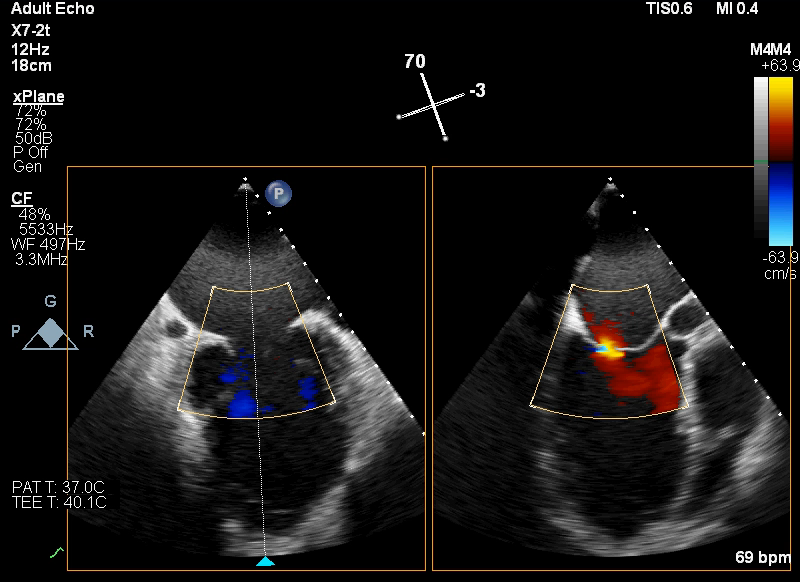

术前TEE显示二尖瓣重度反流,反流主要来源于A2/P2区

患者全麻状态下,在经食道超声心动图和X射线透视引导下,采用股静脉入路,将申淇淇麟®系统瓣膜夹顺利送至二尖瓣A2/P2区域,经调整位置使瓣膜夹垂直对合缘后跨瓣。应用申淇淇麟®系统单瓣叶独立捕获功能,先后捕获二尖瓣前叶和后叶。经超声心动图反复确认瓣叶夹持牢固, A2/P2区域反流量减少,瓣膜夹M侧(3区)残余少量反流。经手术小组专家讨论,决定在M侧植入第二枚瓣膜夹。第二枚瓣膜夹植入之后,经超声心动图反复确认瓣叶夹持牢固,二尖瓣反流减少,跨瓣压差为3mmHg。释放后,经超声心动图和DSA影像评估,双瓣膜夹均夹持稳定,位置和功能良好,效果满意。这一颇具难度的病例手术获得圆满成功。

TEE显示,二尖瓣夹植入后反流减少